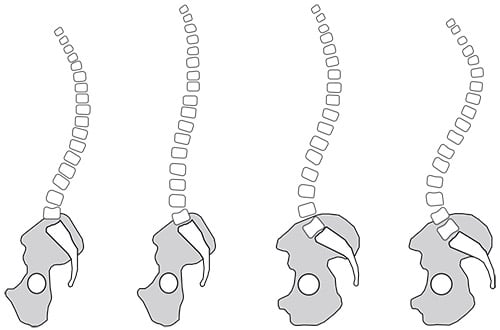

Kyphosis is a term used to describe the direction of the spine’s curvature as seen from the side-view of the body. Namely, kyphosis refers to a forward (“anterior”) curvature of the spine. This is opposite from lordosis, which refers to a backward (“posterior”) curvature of the spine.

A normally aligned spine will have lordosis in the lumbar region (lower back) and cervical (neck) region, and kyphosis in the thoracic (chest) region.

The amount of curvature in each part of the spine must be proportional for a person to stay upright. For example, viewed from the side, some people have spines that look like an “S,” while others have spines that are straighter. In other words, people with a lot of lordosis in the lumbar spine usually have more kyphosis in the thoracic spine in order to keep their entire body balanced.

The spine viewed from the side with the person facing to the left. There is a spectrum of normal spine shapes. Notice that some spines have greater curves than others.